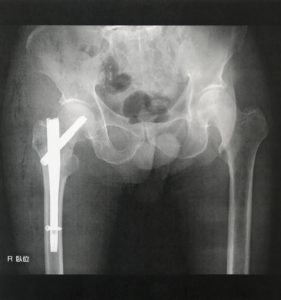

これは、受傷時(整復前)のレントゲンです。明らかに骨折していますね。

整復前―骨折線 症例➀

➀骨折線は、頚部と転子部どちらにあるでしょうか?これが転子部側にあればあるほど、

関節包外のため骨膜性疼痛が出やすく、出血も多く腫脹も大きくなりやすいです。ただ転子部は骨膜がある分骨癒合はしやすいです。

逆に頚部に近ければ近いほど、関節包内のため骨膜性疼痛が出にくく、出血も少なく腫脹も小さいです。しかし、骨膜由来の骨癒合がない分、骨癒合はしにくいですね。

よって、このレントゲンを見るとどうでしょうか??

正直、かなり微妙なところに骨折線が入っています。

なので、頚部と転子部の間の頚基部か?とも考えられます。

これが一番難しく、先ほど説明した頚部と転子部それぞれの特徴両方を少しずつもっているというわけです。

※ちなみに、診断名は大腿骨転子部骨折です。ただ線だけを見ると頚部にもあるか?というニュアンスですね。

よって、ある程度の痛み、腫脹、骨癒合のしにくさはあるか・・・

とこの骨折線で予測されます。

整復前―内側骨皮質 症例➀

では次に、ここをみていきます。

内側骨皮質というのは、この辺りの場所を指します。少々画質が荒いですが💦

なぜここが大事か?

ここは、荷重時に体重が伝わる部分とされています。

なので、ここの骨折がある場合、立位や歩行といった荷重が必要な時に体重がのりにくい可能性が非常に高くなります。

※ただ、あくまでこれは術前の骨折した時の話です。実際に歩行をする時は、骨片を整復し手術をした後の状態なので、術前の内側骨皮質をみるのは、あくまで予測程度に過ぎません。

例えば、内側骨皮質のズレがどれだけあるかを整復前画像で確認し、整復後にどれだけそのズレが減っているか?が重要となるわけです。

もしズレがかなりなくなっていれば荷重はのりやすくなっているでしょうし、ズレが大きいままでは、いわゆる【整復不良】となり歩行獲得に時間を要します。

本症例の場合、内側骨皮質は遠位は残存していますが、近位はズレていますね。

よって、先ほどの説明通り考えると、このズレが整復後の画像でなくなっているか?を機確認します。

整復後―内側骨皮質 症例➀

いかがでしょうか?

整復前は、近位の内側骨皮質がずれている状態でした。

画像を見てみると、整復後はしっかりと整復されているのが分かります。

よって、内側骨皮質のズレによる荷重伝達障害、痛みはかなり少ないのではないか?と考えます。

この荷重時の予測はそのままリハビリに応用出来ますが、言い換えると、この整復状況にも関わらず疼痛が強ければ、骨の問題は低く、骨格筋や創部の問題を疑ったりも出来ます(^-^)